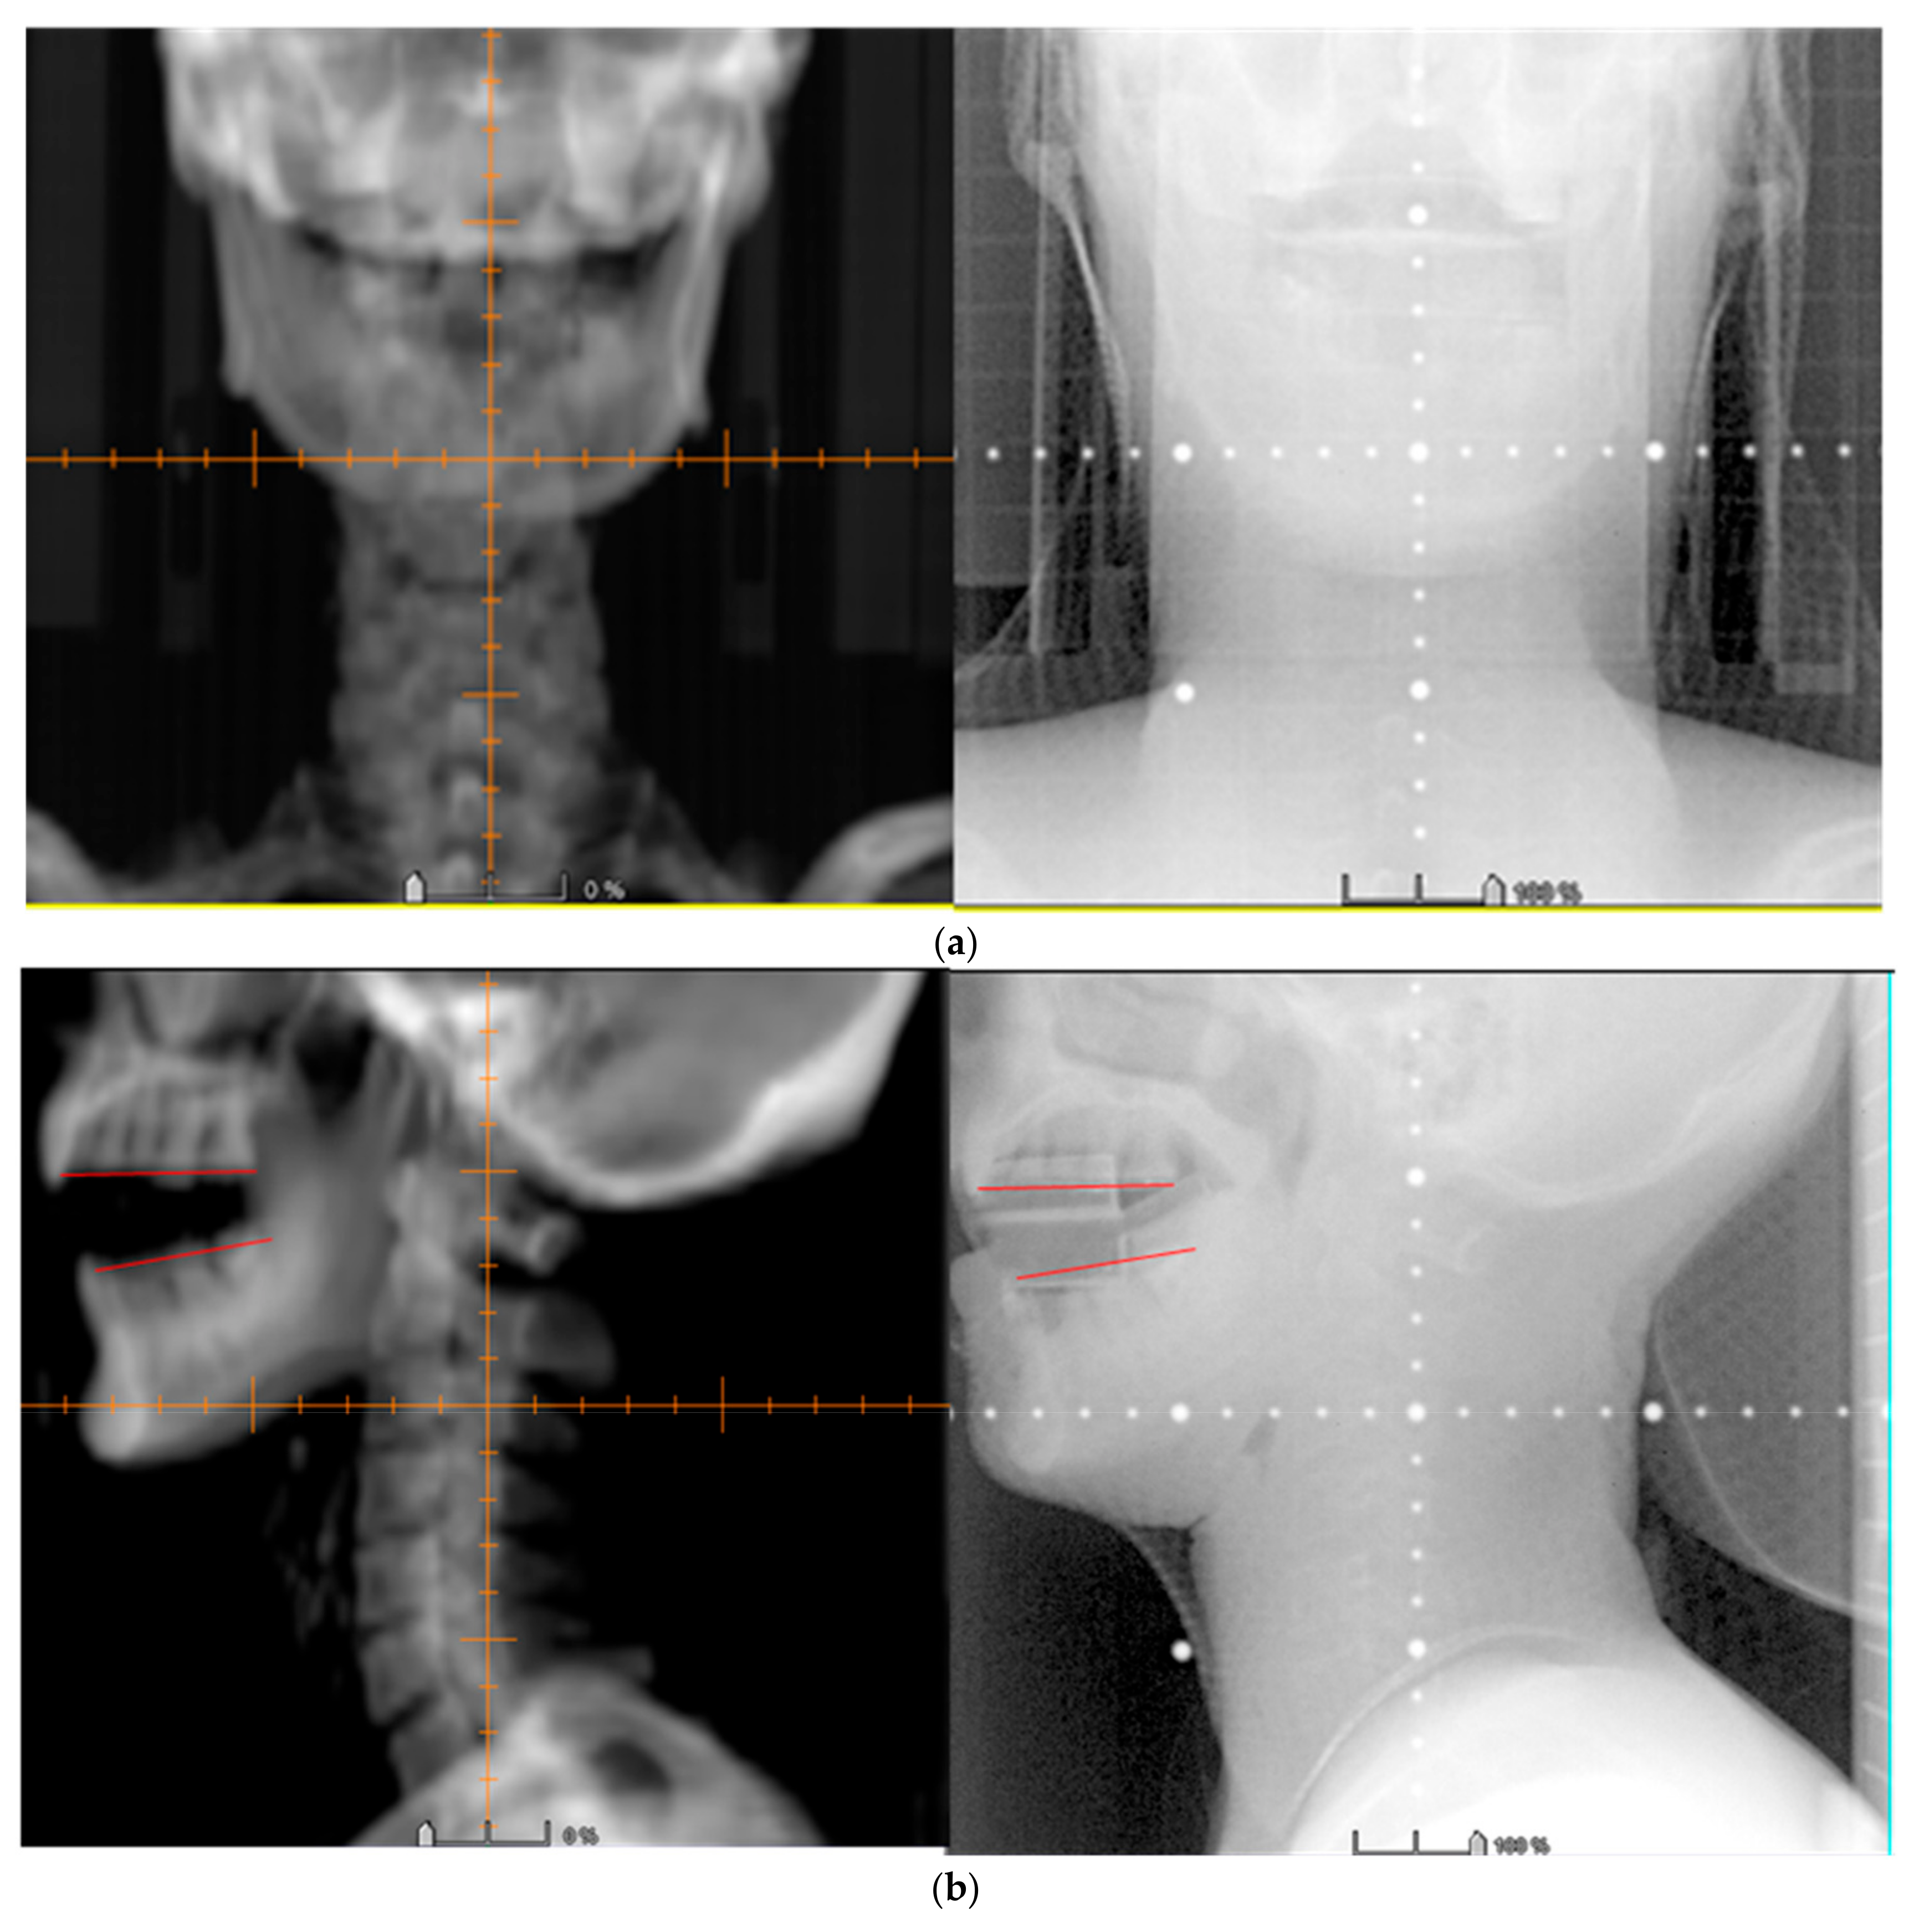

2.9. Images Verification

3.3. Image Verification